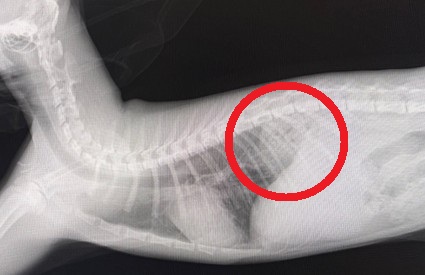

横隔膜が鮮明かつ肺がクリア

横隔膜が不鮮明かつ胸腔に腹腔内臓器が入り込んでいる

胸腔に胃が入り込んでいるのを確認

胸腔内に胃が入り込んでしまっているのが分かります。